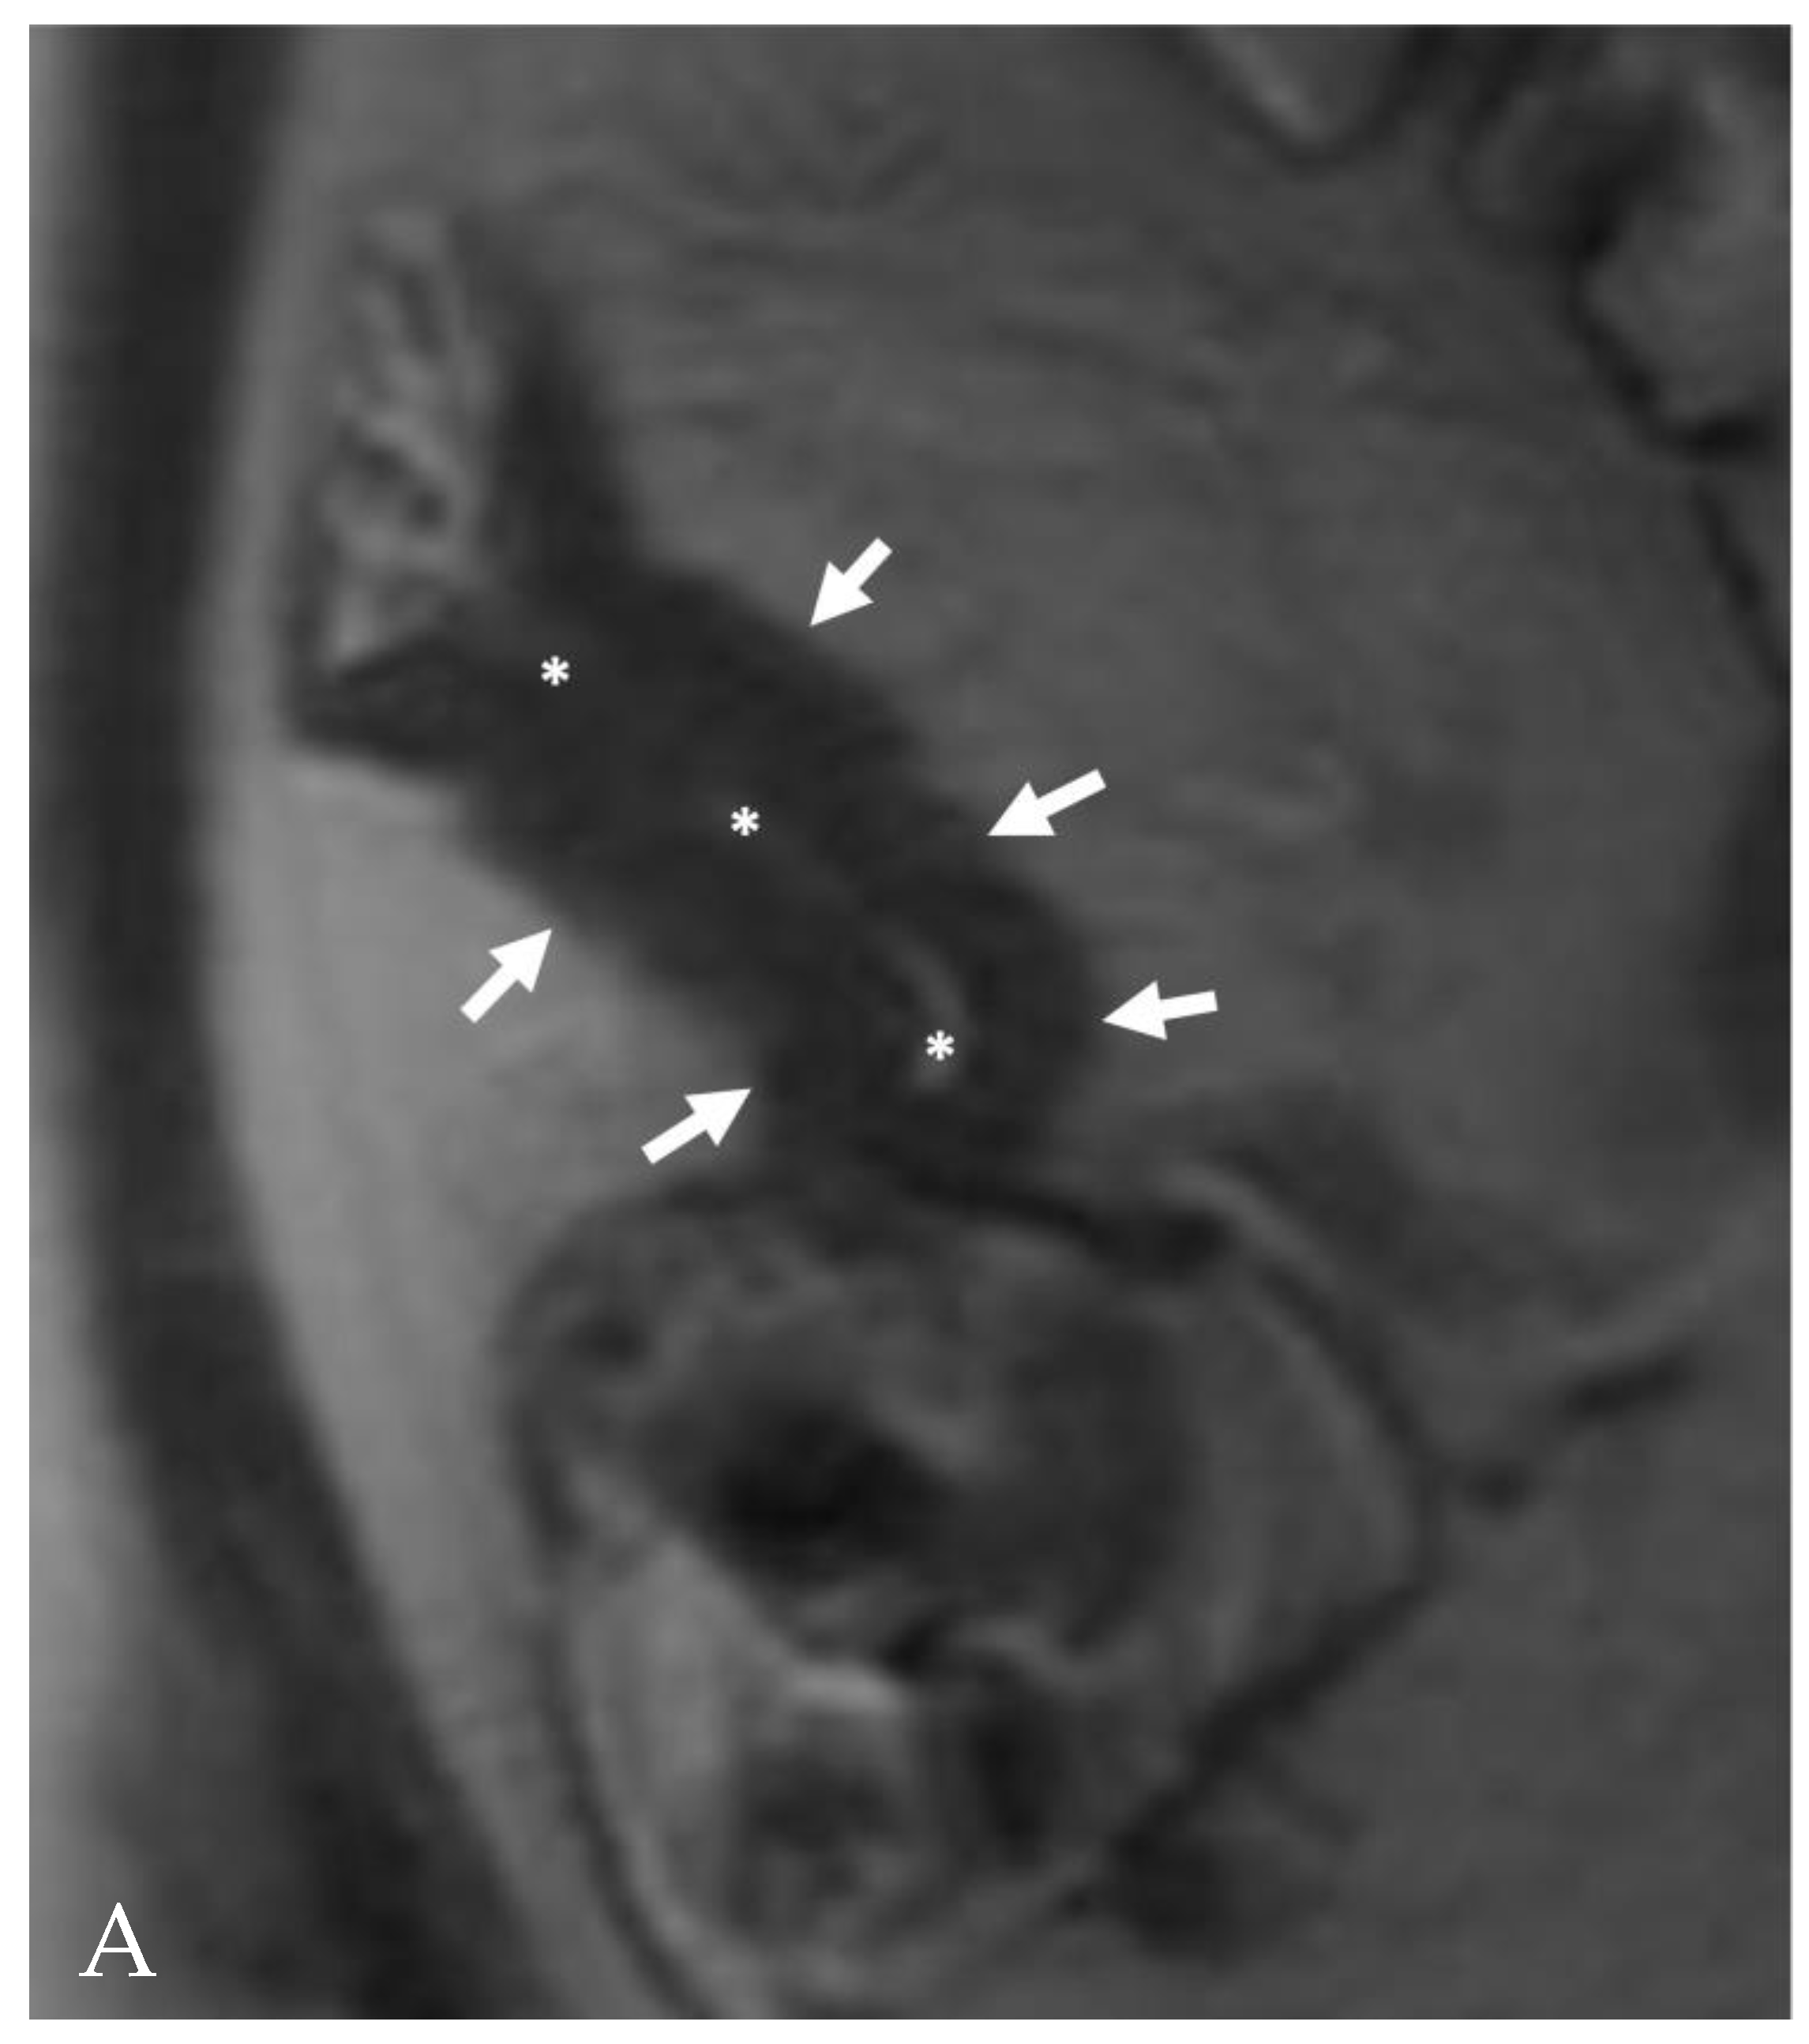

- A normal bowel loop caliber ranges between 2 and 2.5 cm. A bowel lumen is dilated when it has a maximum diameter greater than 2.5–3 cm. The dilation is mild when the upstream lumen is dilated up to 4 cm and severe when it is more than 4 cm (Figure 3) [24]. Pre-stenotic bowel dilatation should always be checked, as it is a sign related to bowel obstruction. Moderate to severe stenosis was determined via double-contrast imaging (conventional barium study) with a sufficient amount of injected air, and stenosis was defined as stenosis in which the lumen was less than one half that of neighboring healthy intestine [25].